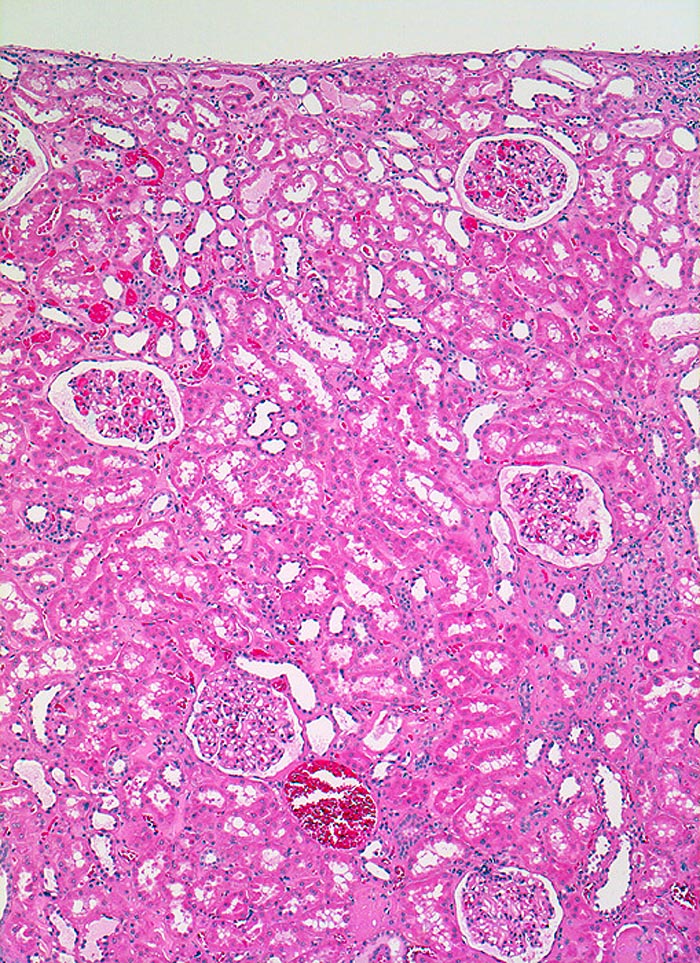

Morphologie:

Je nach Grösse des verschlossenen Gefässes sind unterschiedlich grosse (wenige Millimeter bis mehrere Zentimeter) solitäre oder multiple scharf begrenzte Herde erkennbar. Nach etwa einer Woche imponiert der akute Infarkt als gelber erhabener Bezirk mit 2-5mm breitem rotem Randsaum. Subakute Infarkte bilden flache homogene rote Herde. Nach Monaten bildet sich eine scharf begrenzte weisse Narbe aus. Infolge unterschiedlicher Kollateralversorgung z.B. via Arteria spermatica oder ovarica führt der Verschluss der Arteria renalis nicht immer zur Totalnekrose. Das Endstadium grosser Infarkte bildet die grob gebuckelte Infarkt-Schrumpfniere.

Akute Infarkte bilden histologisch scharf begrenzte kokardenförmig aufgebaute Herde mit zentraler Koagulationsnekrose umgeben von einem Saum neutrophiler Granulozyten. In der Peripherie ist das partiell geschädigte Gewebe ödematös hämorrhagisch und enthält dilatierte hyperämische Gefässe. Die Nekrose wird durch neutrophile Granulozyten und Makrophagen abgebaut und durch Granulationsgewebe ersetzt, welches zu einer gefässarmen Narbe schrumpft. Die äusserste Rindenzone bleibt infolge der Kollateralversorgung durch Kapselgefässe oft vom Infarkt ausgespart. Infarktnarben können wie alle Narben verkalken.